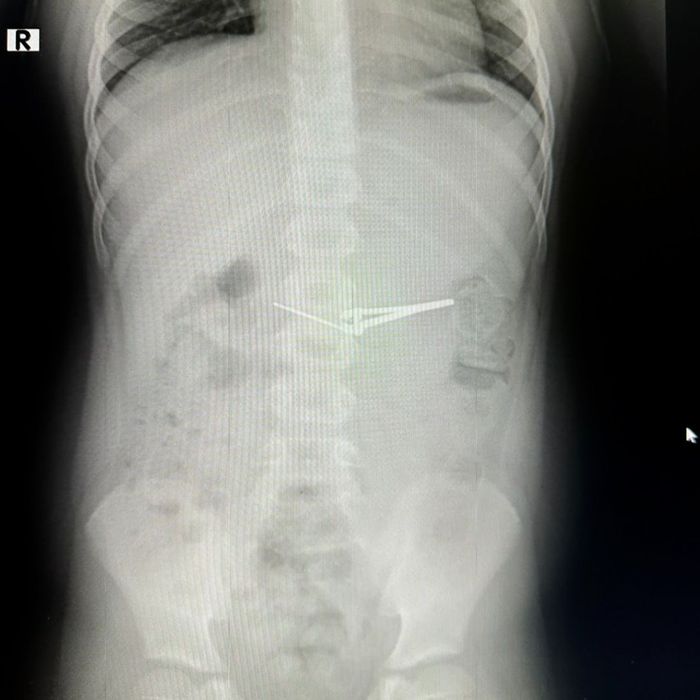

Шестилетний ребенок, пока взрослые не видели, стащил щипчики и по какой-то причине решил попробовать их на вкус. Удивительно, но это не причинило мальчишке ни боли, ни даже особого дискомфорта, и он спокойно поехал с родителями в больницу. Медики сделали рентген и сообщили, что ребенку необходима операция.

Мальчику ввели обезболивающее, а затем, с помощью специального инструмента, так называемой эндокорзинки, аккуратно извлекли щипчики из желудка ребенка. Действовали при этом хирурги так аккуратно, что не задели ни слизистую, ни пищевод.